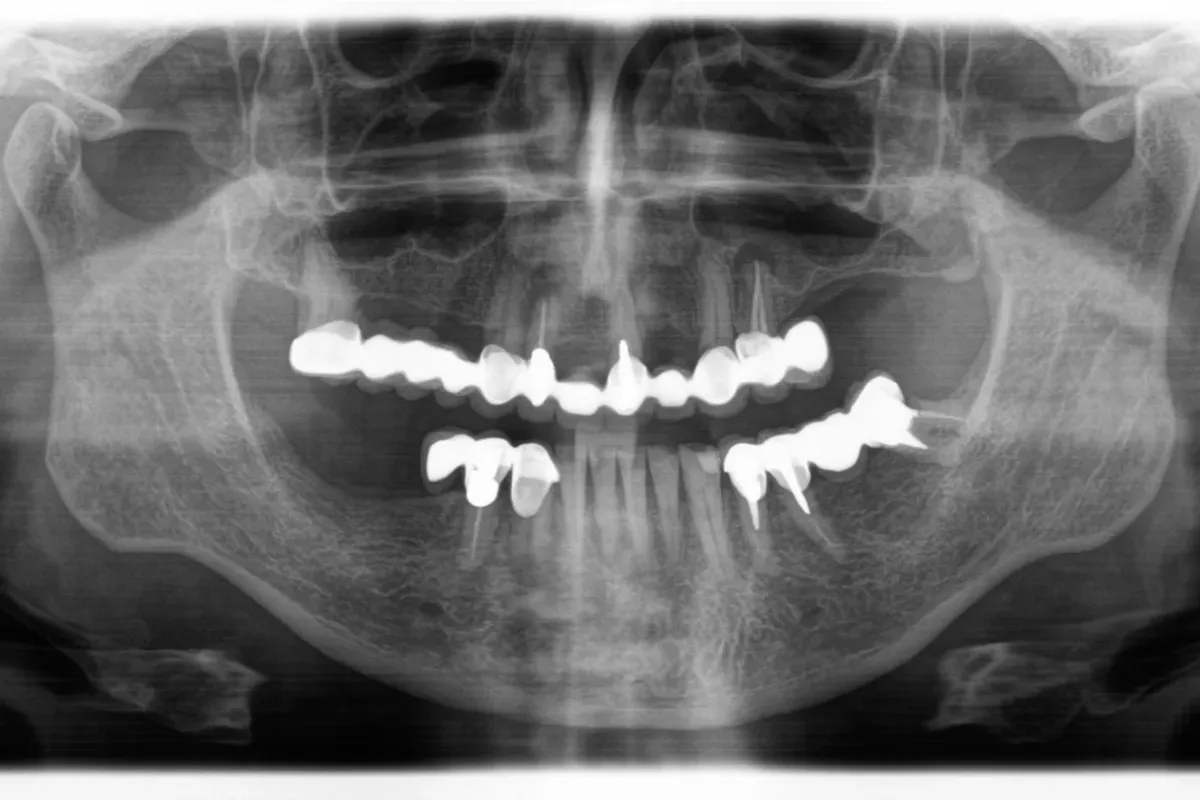

Pristupamo reviziji kada infekcija perzistira ili se ponovno aktivira nakon prvotnog liječenja. U takvim situacijama zub može ponovno postati bolan, osjetljiv na zagriz ili pritisak, a ponekad dolazi i do oticanja okolnih tkiva. RTG snimkom vidljiva je upala oko korijena, što upućuje na neuspjeh primarne terapije.

Prvi kontrolni pregled najčešće se planira nakon šest mjeseci, kako bi se putem rendgenske slike procijenilo povlači li se upala. Potpuni oporavak i regeneracija koštanog tkiva proces su koji traje, ali ako je zahvat kvalitetno izveden i pacijent se pridržava uputa, prognoza je izuzetno povoljna.